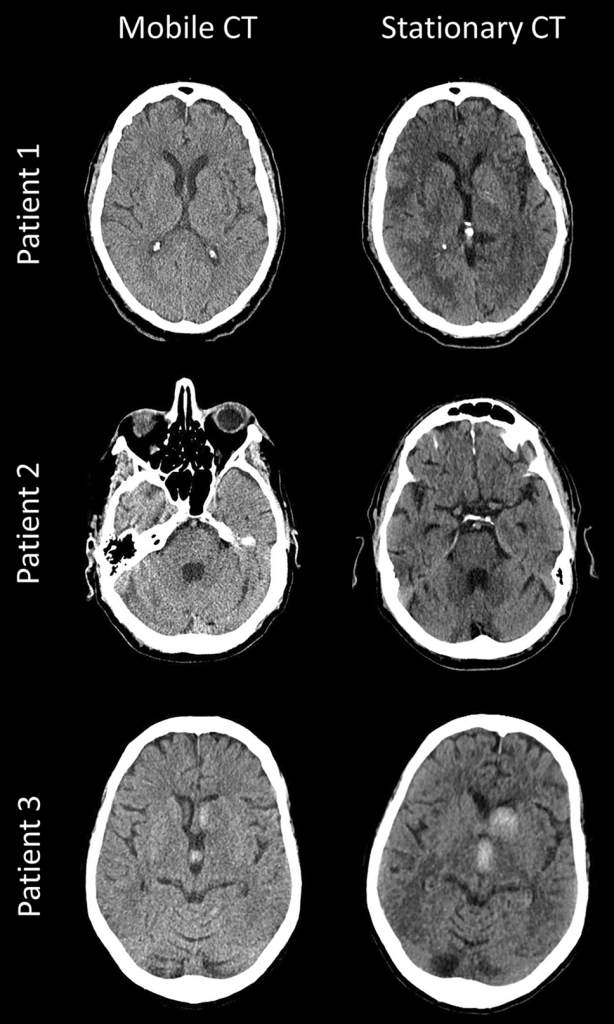

4)Computed Tomography (Ct scan):=

આ મેડિકલ ઈમેજીંગ ટેકનીક છે કે જેમા brain parts ના મલ્ટીપલ ઈમેજિંગ લેવામાં આવે છે.

Ct scan એ મુખ્યત્વે એ brain મા haemorrage, cyst, oedema, infraction, Brain Atrophy હોય તો તેને Assess કરવા માટે યુઝ થાય છે.